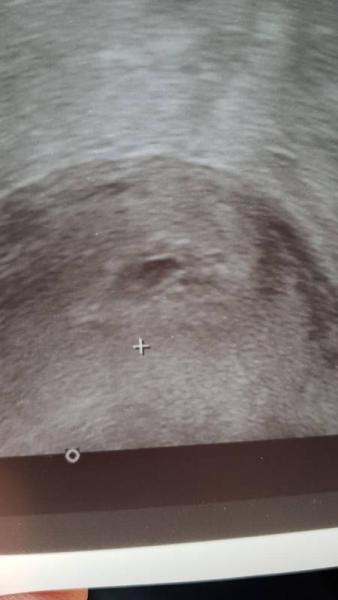

Müsste laut ovi und schwangerscahftstest eigentlich schon 6+2 sein. Soll nun in 2 Wochen nun wieder kommen.

Bild zu Wer erkennt was? - Schwanger - wer noch? Rund um die Schwangerschaft

Nach der 7. Woche sieht das nicht aus. Aber nach einer Fruchthöhle mit Inhalt. Der Arzt könnte sich mal ein neues US-Gerät anschaffen.

Antwort auf Beitrag von Pebbie

War auch mein erster Gedanke. Was für ein scheiß US-Gerät.